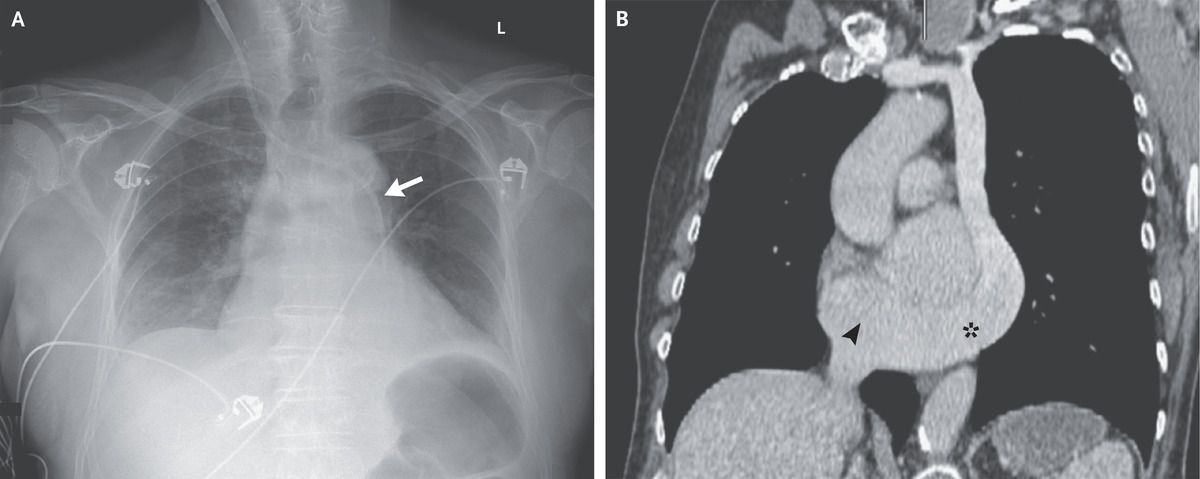

A 79-year-old man with a history of urinary retention that had been treated with an indwelling urinary catheter was admitted to the intensive care unit for septic shock. On hospital day 1, ultrasonographic guidance was used to insert a hemodialysis catheter into the right internal jugular vein to initiate renal replacement therapy for oliguric acute kidney injury. A chest radiograph obtained after the procedure showed the catheter crossing the midline at the level of the manubrium and entering the left mediastinum (Panel A, arrow). Arterial placement of the catheter was initially suspected, although blood gas analysis was consistent with venous placement. Retrospective review of recent computed tomographic images of the chest (Panel B) showed an isolated persistent left superior vena cava coursing along the left mediastinum and subsequently connecting with a large coronary sinus (asterisk) that drained into the right atrium (arrowhead). A persistent left superior vena cava, which is often detected incidentally, is the most common anomaly of the thoracic venous system. It typically occurs simultaneously with a right superior vena cava, which was not found in this patient. Culture of a urine specimen from this patient grew Escherichia coli. After treatment with vasopressors, antibiotic agents, and renal replacement therapy, the septic shock and acute kidney injury resolved. The hemodialysis catheter was removed without complication.